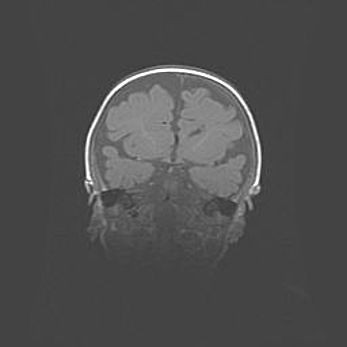

Открытая гидроцефалия.

Возраст: 6 месяцев 15 дней

Вес: 6200 г

Пол: женский

Окружность головы: 41 см

Срок гестации: 38 недель

Гидроцефалия головного мозга у новорожденных – это скопление избыточного количества цереброспинальной жидкости в головном мозге. Ее избыточное скопление в мозге приводит к патологическому расширению желудочков мозга (четырех полостей, расположенных в глубине белого вещества мозга, заполненных цереброспинальной жидкостью и связанных узкими проходами).

Открытый тип гидроцефалии (сообщающаяся) наблюдается тогда, когда нарушен механизм всасывания ликвора в системный кровоток. При этом типе причиной заболевания чаще всего является перенесенные ранее инфекции (например: менингит),  либо же наличие крови в субарахноидальном пространстве.